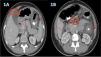

Se comparte el caso de una mujer de 40 años, con antecedentes de rinitis alérgica, en condición puerperal tardía; sin precedente de viaje reciente, uso de herbolario o nuevo fármaco. Ingresó al Servicio de urgencias por un cuadro clínico de 15 días de evolución de dolor e incremento de perímetro abdominal, asociado a diarrea y vómitos. En el hemograma realizado se identificó una marcada eosinofilia (9.460x mm3) sin alteración de otras líneas celulares; ecografía abdominal con ascitis moderada y coprológico con sangre oculta positiva sin parasitosis. Se realizó una tomografía abdominal con contraste, que documentó engrosamiento gástrico antral, duodenal y en ángulo esplénico del colon, con adenomegalias paraaórticas, mesentéricas y líquido libre intrabdominal (fig. 1 A y B); en el tórax no presentó alteraciones. Se realizó una paracentesis, encontrando líquido ascítico con abundante celularidad inflamatoria (fig. 2A) (eosinófilos, 70%; neutrófilos, 10%; linfocitos, 3%; histiocitos, 6%; plasmocitos, 1%, y mesoteliales, 10%), sin células malignas, cultivo negativo y adenosina desaminasa (ADA) en 80 U/L. La esófagogastroduodenoscopia permitió observar una mucosa gastroduodenal muy congestiva. La histopatología duodenal evidenció atrofia vellositaria duodenal focal e incontables eosinófilos dispuestos en sábanas, con permeación del epitelio glandular (fig. 2B). Se realizó colonoscopia con toma de biopsias aleatorias por segmentos, incluyendo íleon. Durante el estudio endoscópico no se identificó la mucosa alterada, tampoco se observaron hallazgos relevantes en los reportes de patología documentados. En otros paraclínicos realizados se identificó que la IgE estuvo tres veces por encima del límite superior de normalidad acompañada de hipoalbuminemia leve. Para el diagnóstico diferencial, se realizó un análisis bioquímico, hepatorrenal, electrolítico, serología del virus de la inmunodeficiencia humana (VIH), toxoplasma, vitamina B12, factor reumatoide, anticuerpos antinucleares, anti-ADN, anticuerpos anticitoplasma del neutrófilo (ANCA), triptasa sérica, IgG, IgM e IgA. Todos los resultados arrojaron parámetros normales. La citometría de flujo sanguíneo e inmunohistoquímica de tejidos gastrointestinales descartaron compromiso neoplásico. Por su parte, la prueba de tuberculina (PPD) se registró como no reactiva. Se concluyó la existencia de GEE, y se inició el tratamiento por vía oral con prednisona, 40mg por día, con resolución de los síntomas a las 72 horas y descenso del perímetro abdominal y control normal de eosinófilos en sangre a las dos semanas. Se suspendió progresivamente el tratamiento después de ocho semanas. Actualmente, la paciente permanece asintomática, con recuento eosinofílico normal y control de resonancia magnética de abdomen y pelvis con contraste sin hallazgos de anormalidad.